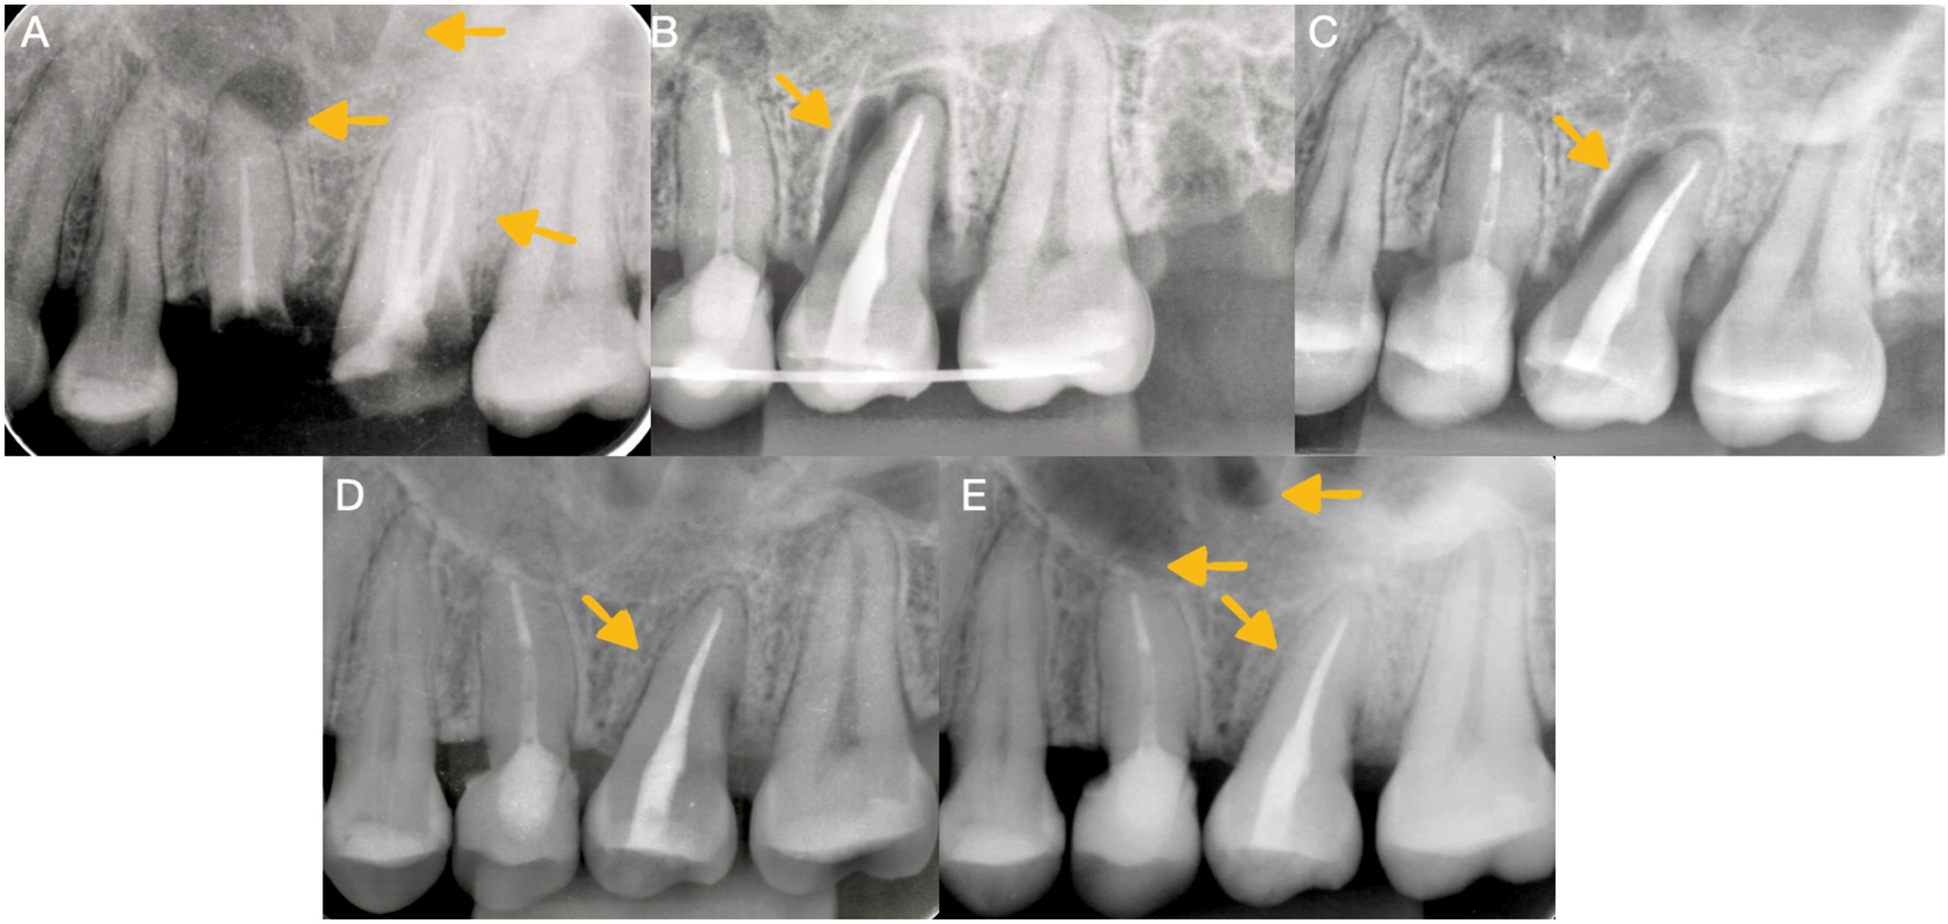

In the initial periapical radiograph (Figure 1A), a deep caries invading the middle third of the distovestibular root was observed at the level of the right upper molar, and a fracture of the palatal, mesial, and distal walls was clinically observed. In addition to extensive caries at the level of the dental crown and inadequate obturation of the root canals, in the right upper premolar, a coronal fracture, exposure of the obturation material, and inadequate obturation of the canal with the presence of a periapical abscess were observed.

Figure 1. Radiographic imaging. (A) Initial radiograph of the first maxillary upper molar before retreatment and autotransplantation showing radiolucency in the right maxillary sinus. (B) Control radiograph of the autotransplanted third molar. (C) Radiographic image taken 1 month after autotransplantation. (D) Radiographic analysis conducted 1 year after autotransplantation revealed the presence of bone formation and the continuity of the periodontal ligament. (E) A radiographic analysis conducted 2 years after autotransplantation revealed the presence of bone formation and the continuity of the periodontal ligament.

The splint was kept in the mouth for 3 weeks (Figure 1B), after which it was carefully removed. The dental organ had a grade 2 mobility, so an appointment was made for an evaluation and control radiograph the week following the procedure. Subsequently, a decrease in mobility and healing of the adjacent tissues were observed 1 month after the procedure (Figure 1C).

The patient was monitored clinically and radiographically during the first and second years after the autotransplantation procedure (Figures 1D,E) and, in the third year, clinical (Figure 3D) and tomographic evaluations were performed, with adequate soft tissue healing and bone neoformation with continuity of the periodontal ligament at the level of the autotransplanted dental organ observed (Figures 2D–F).